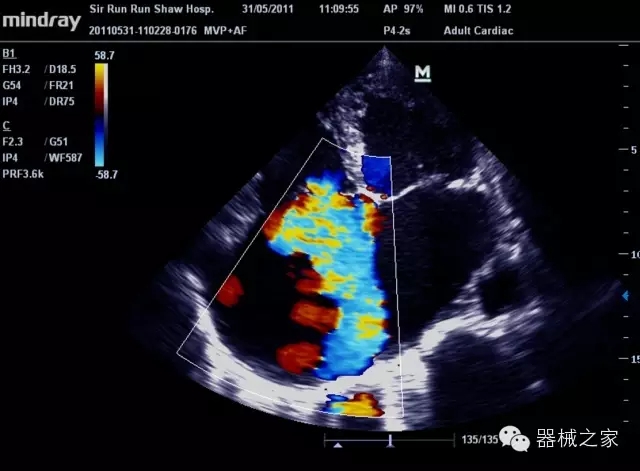

經(jīng)典產(chǎn)品:M7(星鉆)

臨床圖片賞析

產(chǎn)品特點

·裝載有采用Multi-Core多核處理的非嵌入式平臺,成像效率大大提高,并且能夠給用戶帶來高速、多任務(wù)并行信號處理體驗;

·優(yōu)秀的圖像效果、強大的功能體驗、豐富的探頭選擇、合理的便攜式設(shè)計,全中文顯示及病人管理界面,使得M7在任何場合、任何時候都能快速響應(yīng)更好的心血管、腹部、婦產(chǎn)、小器官等常規(guī)超聲檢查以及肌骨、神經(jīng)、顱腦、術(shù)中等新興領(lǐng)域的使用需求;

8倍波束并行處理系統(tǒng)

·在便攜式緊湊平臺上采用更多倍波束并行接收信號處理模式,無論二維還是彩色血流圖像狀態(tài)下,擁有更靈敏的回波頻移捕獲能力,大大提高時間分辨率,尤其使得心血管表現(xiàn)更為突出;

PSHI?寬帶頻移諧波技術(shù)

·在普通組織諧波的基礎(chǔ)上,通過精確控制的波束形成器,發(fā)射兩組具有相位偏差反向的信號,并采用并行信號處理,數(shù)字化合成并采樣回波信號,在高靈敏度的濾波器的處理過程中獲取更純凈的諧波信號,使圖像具有更加出眾的細(xì)節(jié)分辨率;

iClear®+iBeam?

·智能化按線復(fù)合多角度獲取聲束的原始信號,配合智能化的斑點噪聲識別及控制處理技術(shù),整體提高組織結(jié)構(gòu)細(xì)節(jié)分辨率,任何時候都能快速響應(yīng),更好的滿足心血管的使用需求;

支持全新3T工藝探頭群

·包括探頭材料、結(jié)構(gòu)設(shè)計、加工工藝三方面的革新技術(shù)給圖像帶來品質(zhì)的飛躍;

CFDA注冊證編號

·粵食藥監(jiān)械(準(zhǔn))字20132230475